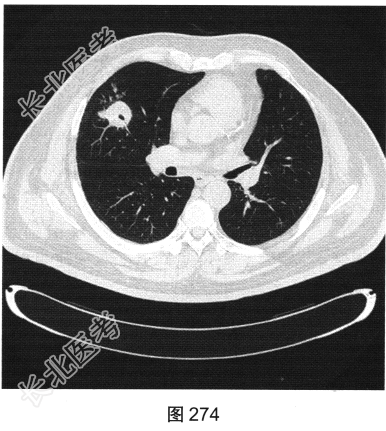

- [材料题] 患者男性,56岁,因“查体发现右肺中叶结节半个月余”就诊。患者于半个月前在小汤山疗养院查体时行胸部X线检查,显示右肺中叶结节,遂至我院就诊。行胸部CT检查:显示右肺中叶外侧段有一肿块影,大小为3.6cm×3.2cm,可见分叶,边缘有毛刺,内见空泡影,CT值约15HU,增强后CT值约25HU。患者近期无咳嗽、咳痰,无咯血、胸痛,无发热、乏力,无声音嘶哑、饮水呛咳,无头痛、头晕,未予特殊治疗。为进一步诊治,以“右肺占位”收入我院。患者精神状态良好,体力、食欲、睡眠正常,体重无明显变化,大、小便正常。胸部CT检查如图274~图277所示。

- 多项选择题1.患者病变的影像特点包括( )

A、右肺中叶结节

B、裂隙样空洞

C、界限清楚

D、血管集束征

E、病变轻度强化

F、可见卫星灶